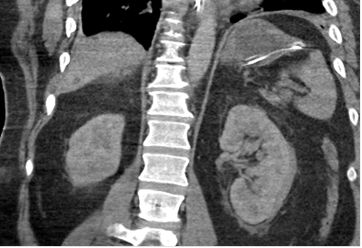

Figures ci-dessus : Accident de moto sur circuit, intubation sur place. Le body-scanner révèle un hématome sous dural supra-tentoriel gauche, de multiples petites contusions cérébrales hémorragiques, une fracture isolée du condyle occipital droit, une contusion du rein gauche avec lame d’hématome sous capsulaire.